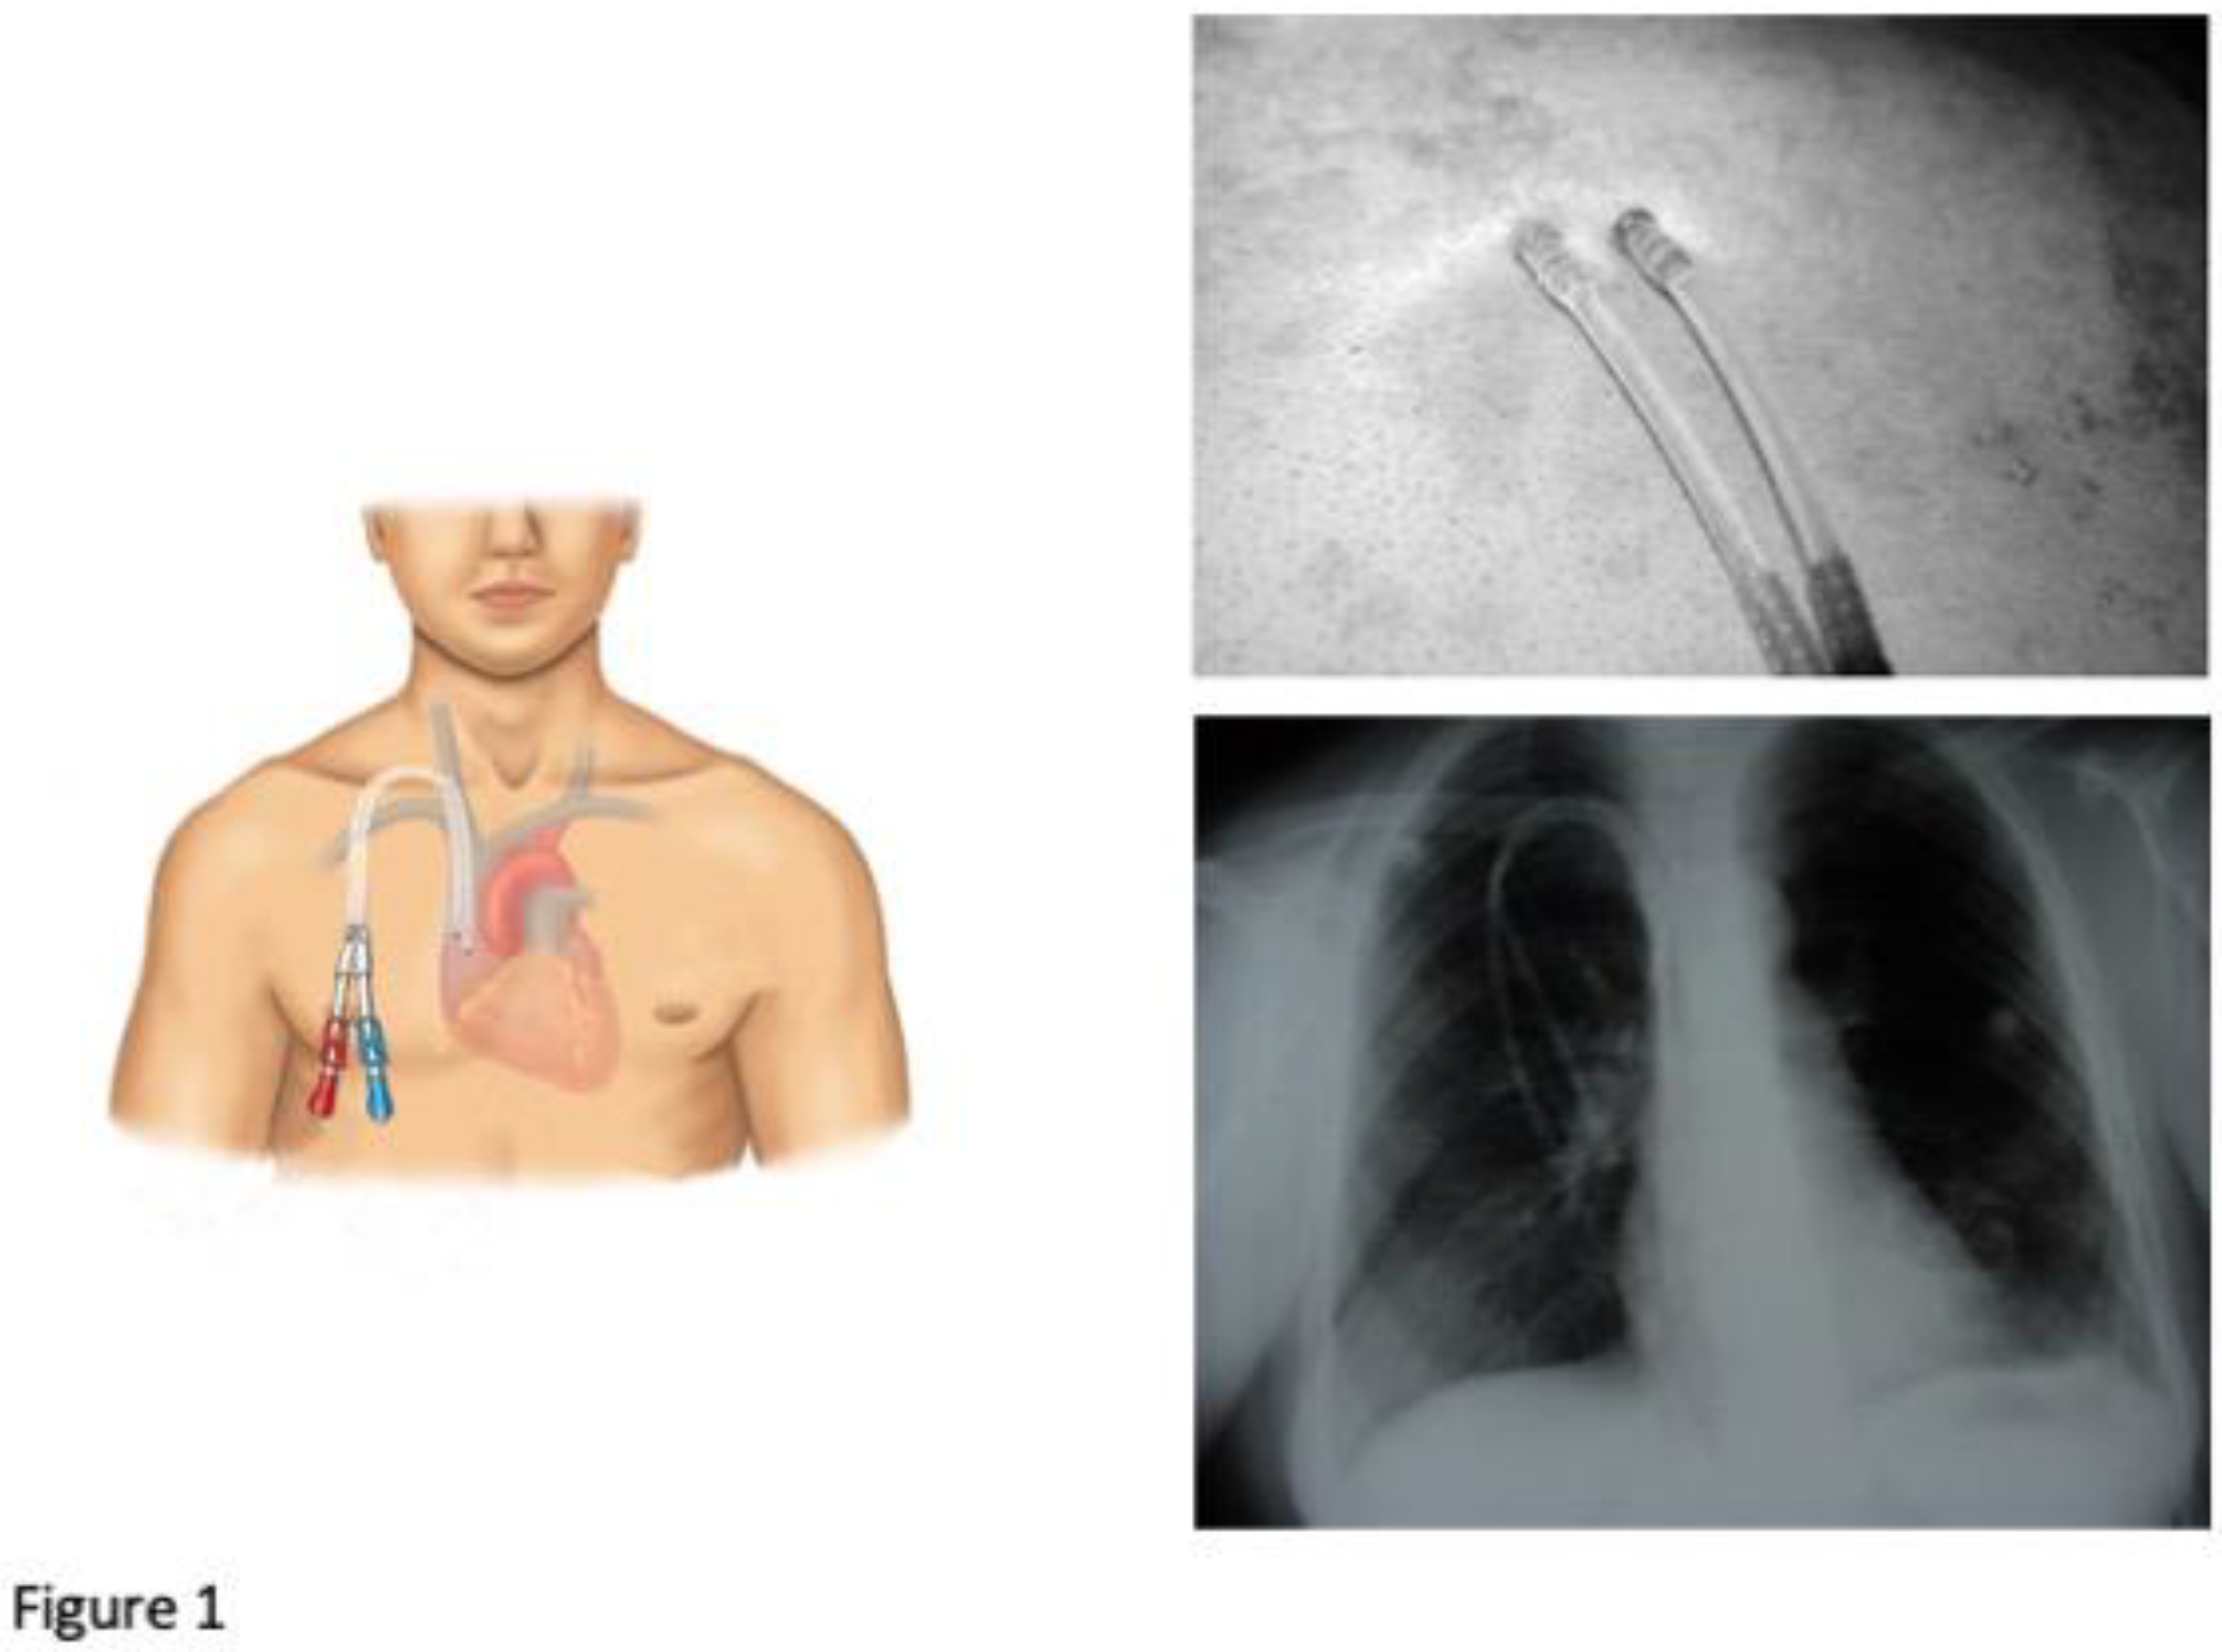

- DualCath Looking and Imaging (Figure 1)